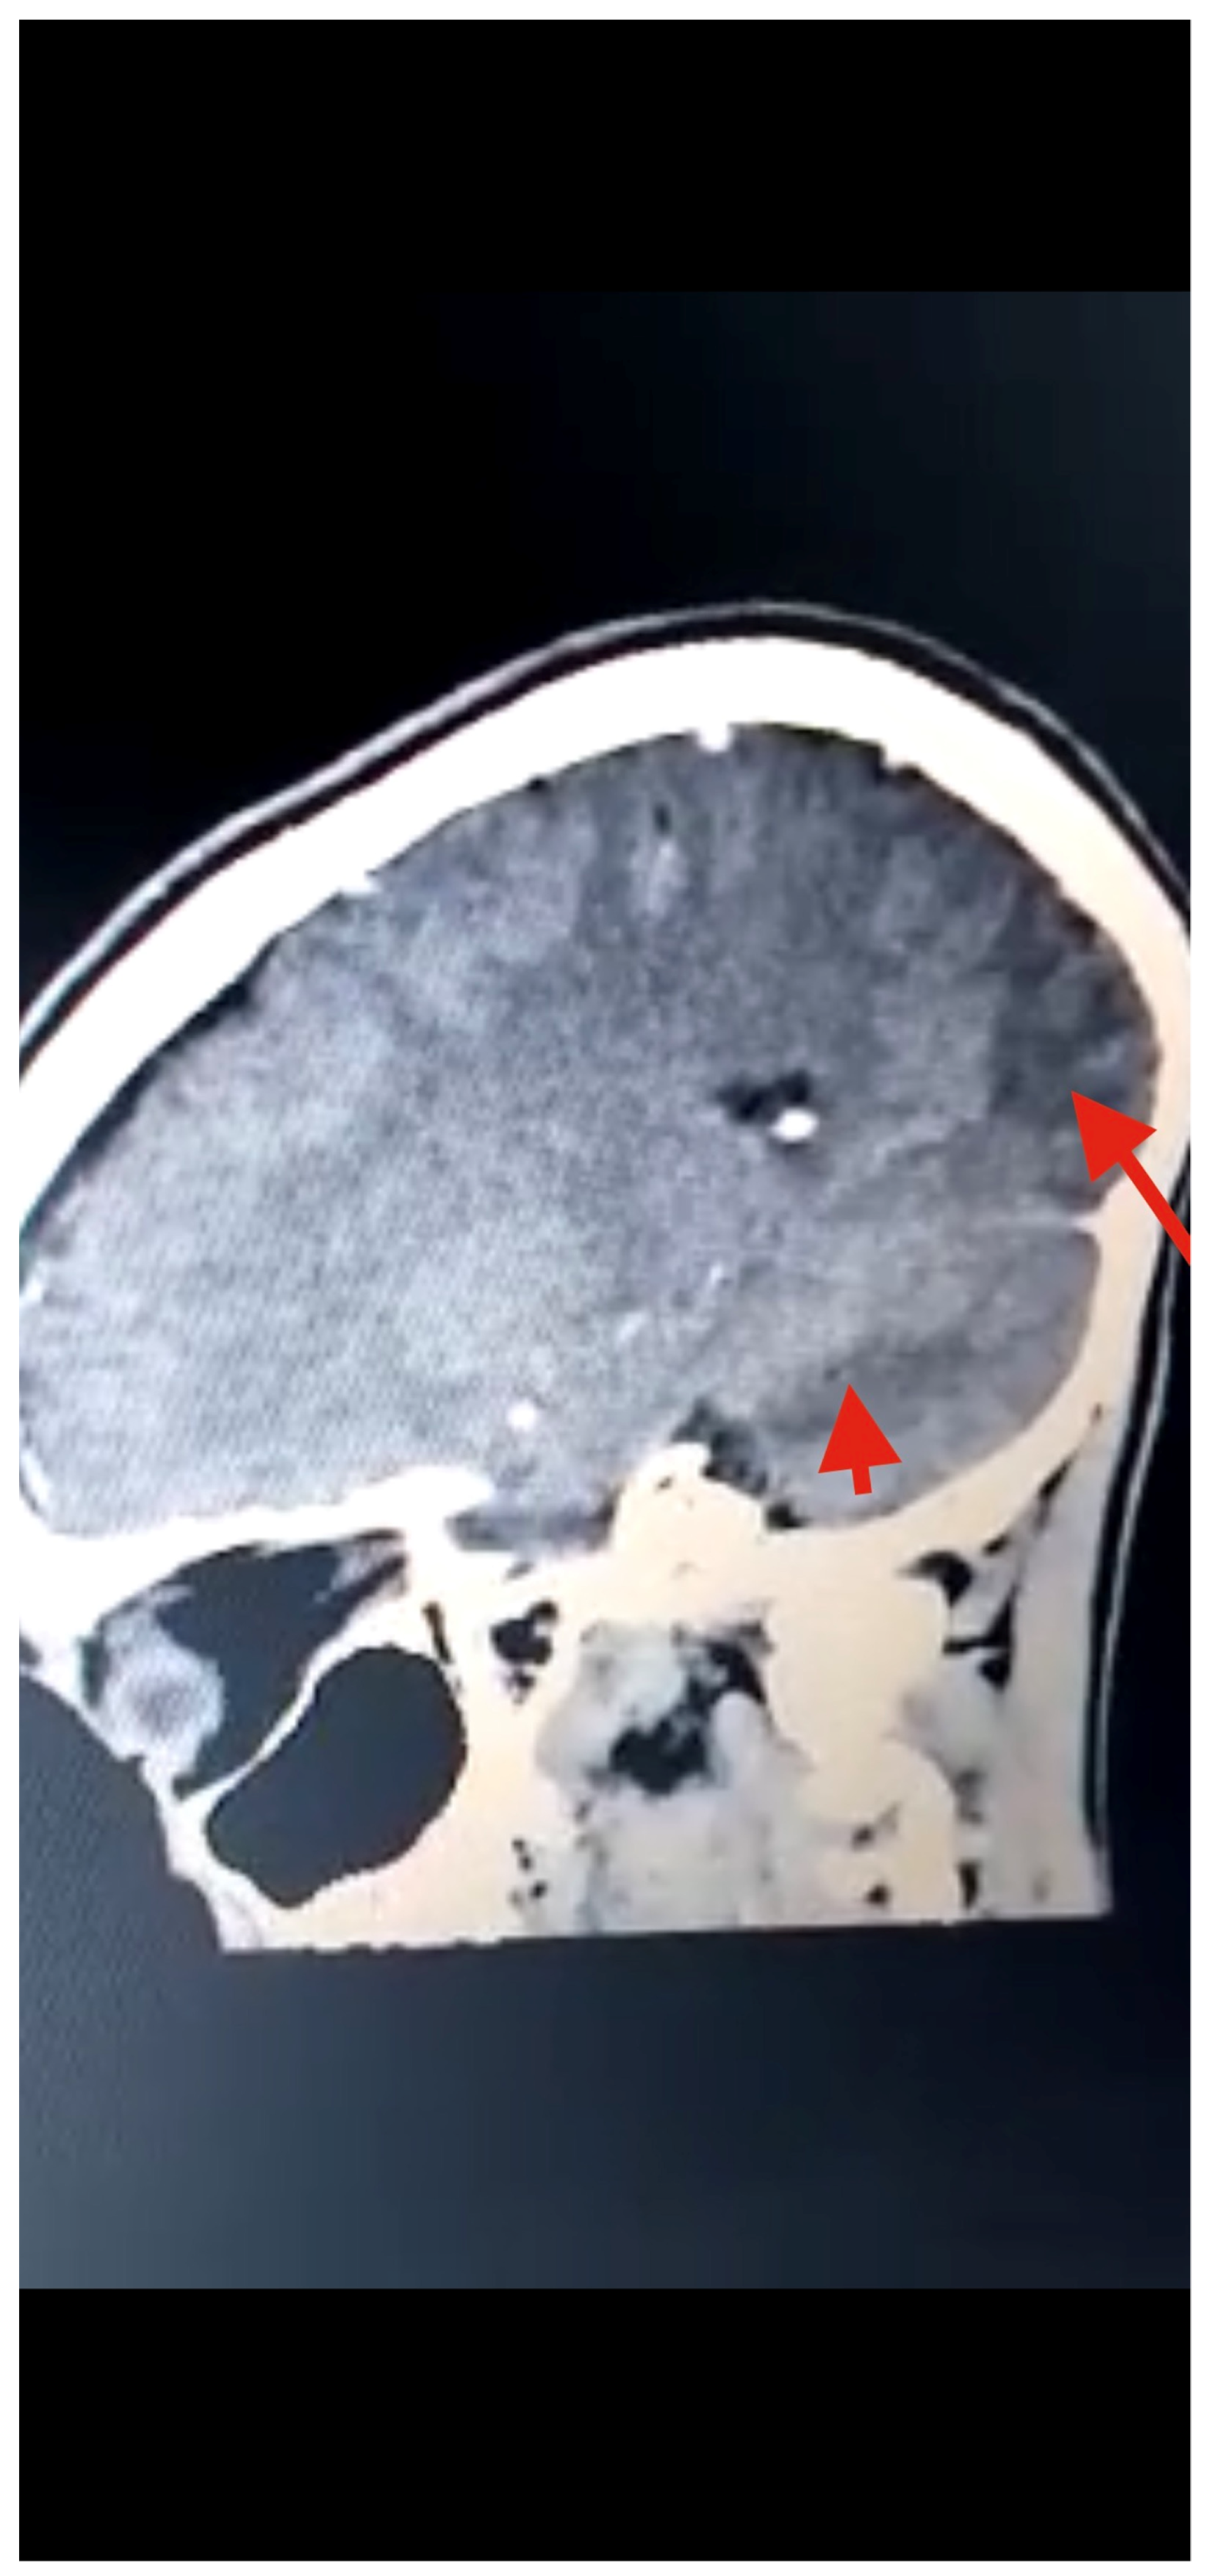

Several diagnostic tests were performed, including complete blood count, urinalysis, stool microscopy test Figure 1, and cerebrospinal fluid analysis Table 1. Serology testing (enzyme-linked immuno-electrotransfer blot) of blood for cysticercosis antibodies to glycoprotein antigens was positive, suggesting cysticercosis. Head computed tomography (CT) scan showed local soft tissue inflammation and multiple cysticerci granulomas due to cysticerci degeneration in the cerebral cortex Figure 2. Brain magnetic resonance angiography (MRA) showed a wedge-shaped T1-weighted hypointense and T2-weighted hyperintense lesion in the body of the right caudate nucleus. Diffusion of contrast was restricted on diffusion-weighted imaging. The lesion measured 2.3 cm in diameter and was suggestive of an acute/subacute infarct Figure 3. There was no restriction of contrast diffusion on DW1, suggesting white matter changes. A final diagnosis of cortical blindness due to NCC and co-infection with a urinary tract infection was made.

Figure 3.

Head CT scan showing multiple T1W hypointense, with T2W and FLAIR hyperintense, areas in the posterior and parietal cortices, indicative of infarction (red arrows) due to stroke from cysticercal invasion of the vascular bed.